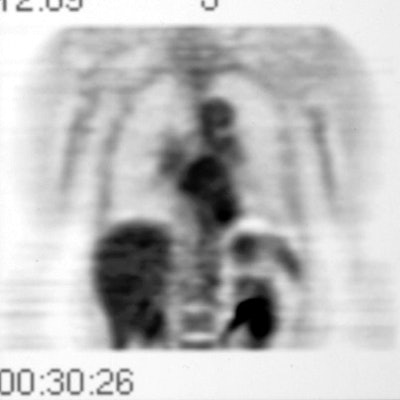

A PET-FDG scan was performed to determine if the lesion demonstrated increased metabolic activity. The lesion appeared as a region of decreased activity above the surface of the left hemidiaphragm. This finding suggested the lesion to be rounded atelectasis which has been shown to not be metabolically active on FDG-PET imaging. The patient had the lesion surgically resected and it was found to be rounded atelectasis and pleural plaque.